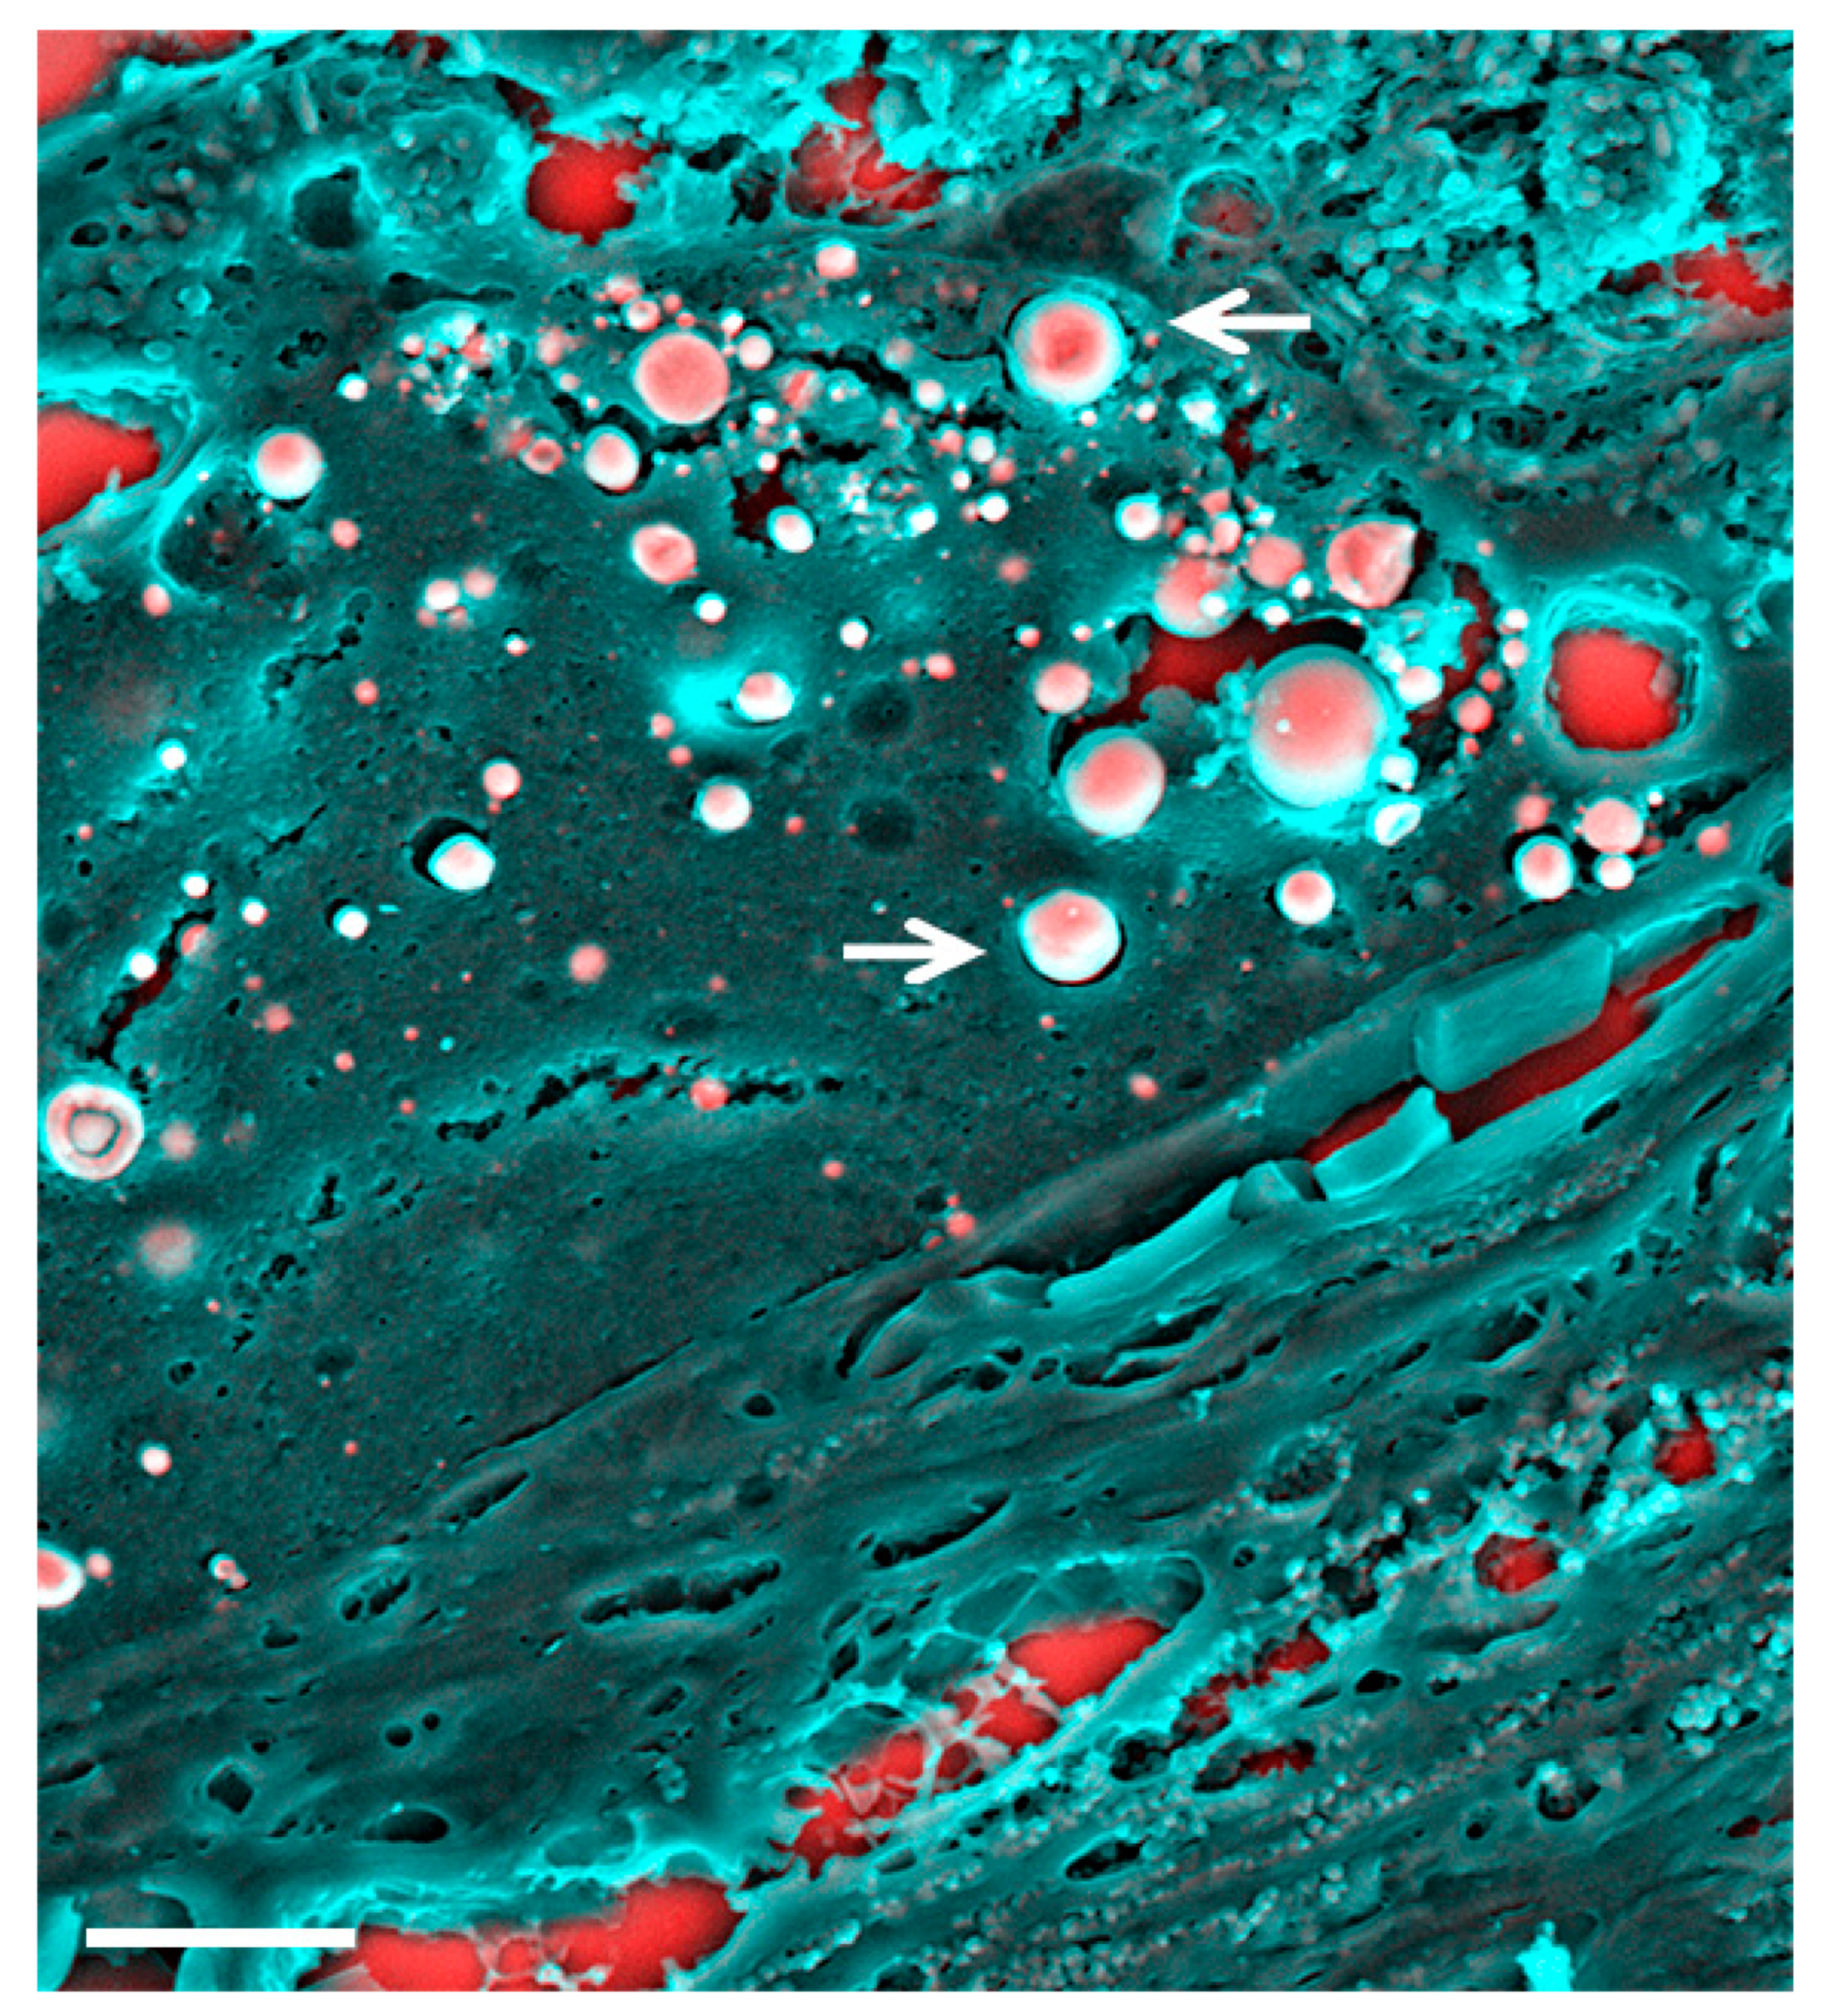

- Bazin, D.; Jouanneau, C.; Bertazzo, S.; Sandt, C.; Dessombz, A.; Réfrégiers, M.; Dumas, P.; Frederick, J.; Haymann, J.P.; Letavernier, E.; et al. Combining field effect scanning electron microscopy, deep UV fluorescence, Raman, classical and synchrotron radiation Fourier transform Infra-Red Spectroscopy in the study of crystal-containing kidney biopsies. C. R. Chim. 2016, 19, 1439–1450. [Google Scholar] [CrossRef]